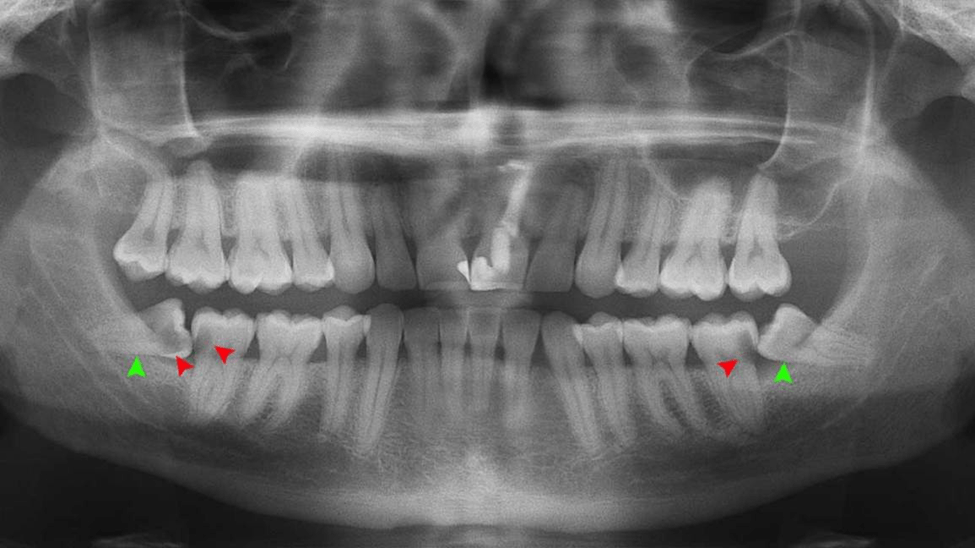

1. Consultation and X-Ray

The dentist evaluates the position of the tooth.

What Is an Impacted Wisdom Tooth?

An impacted wisdom tooth occurs when the tooth does not fully emerge from the gums due to lack of space.

Types of impaction include:

- Horizontal impaction

- Vertical impaction

- Partial eruption

- Fully impacted tooth

Impacted teeth can cause infection, pain, and damage to nearby teeth.